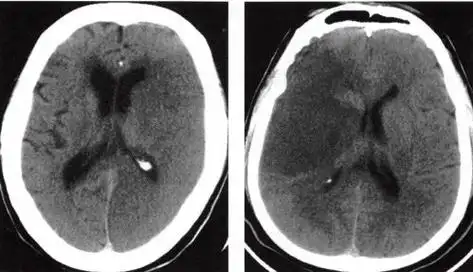

多发性腔隙性脑梗死的临床表现

出血性脑梗塞大脑图片

经典总结急性期脑梗死的影像学特点及几个重要征象建议收藏